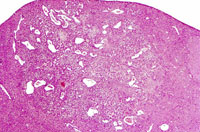

This hemangiosarcoma is well demarcated from the normal hepatic parenchyma; sharp demarcation is an unusual feature of hemangiosarcomas. Large blood-filled lakes are apparent. Higher magnification shows bands of spindle-shaped endothelial cells with attendant destruction of hepatocytes, proliferation of plump endothelial cells, and atrophy of hepatocytes.